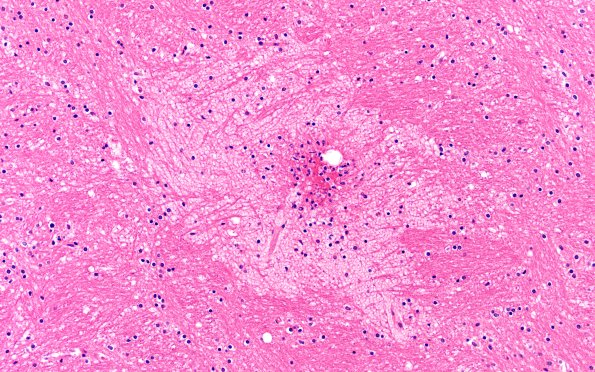

12B9 Fat Embolism (Case 12) int capsule N12 20X

12B9,10 Hemorrhages and infarcts were numerous in the internal capsule. (H&E)